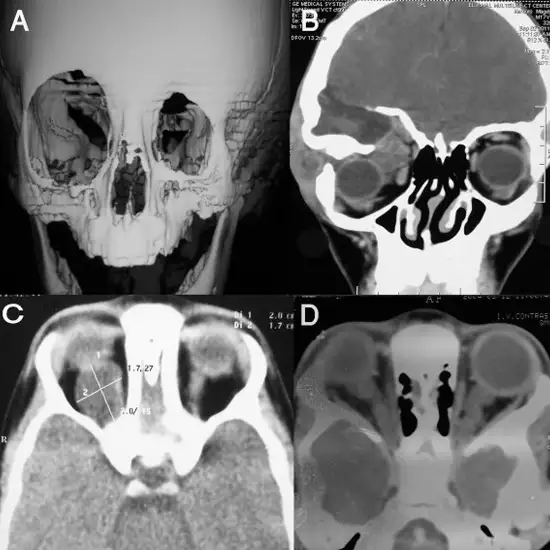

CT Head and Orbit is a Computed Tomography of the head and orbit. It is an imaging scan that takes thin-slice images of the brain, brain stem, and skull, and thin-slice images of the eye and orbital socket at three different angles. This scan is very helpful in diagnosing stroke, trauma, congenital defects, bleeding, and possible masses, injuries, and diseases.